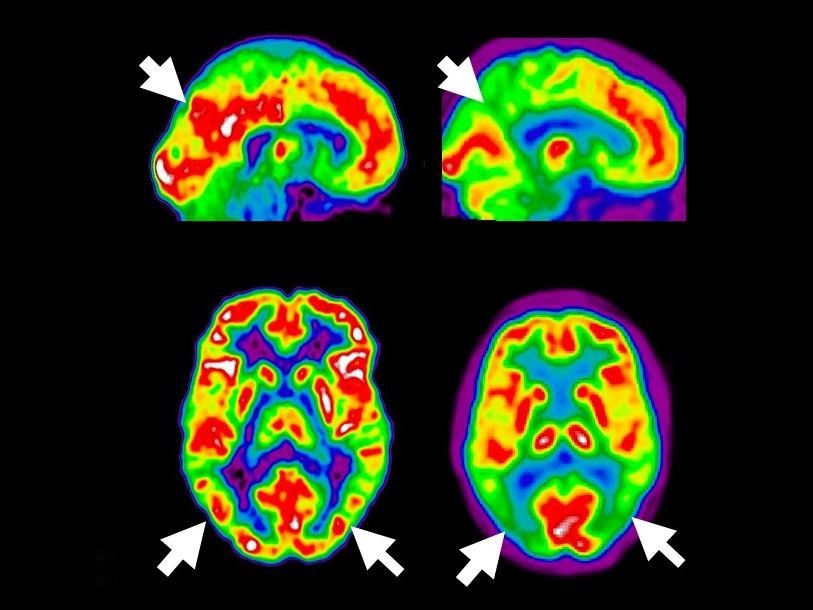

Авторы исследования отмечают, что сложности в лечении болезни Альцгеймера во много вызваны тем, что врачи обнаруживают ее, только когда становятся очевидными нарушения памяти и функциональные расстройства. Современные методы обнаружения болезни Альцгеймера в доклинической стадии дороги, трудоемки и инвазивны. К таким методам относятся обнаружение бета-амилоида или тау-белка в спинномозговой жидкости или же использование позитронно-эмиссионной томографии. Авторы статьи для ранней диагностики предлагают использовать анализ крови.